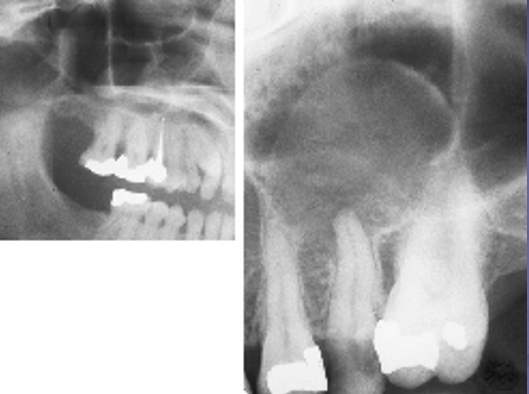

What are these radiographic findings?

Aneurysmal Bone Cyst

✎ A dome shape swelling on the floor of the sinus that’s associated with some _sort of inflammation of tooth of t_he premolar caused inflammation underneath the apex of the bone (right) and then that leads to accumulation of fluid which causes the sinus lining to elevate off the bone and fill with fluid

✎ After root canal therapy and once the infection gets under control, these will typically resolve on their own